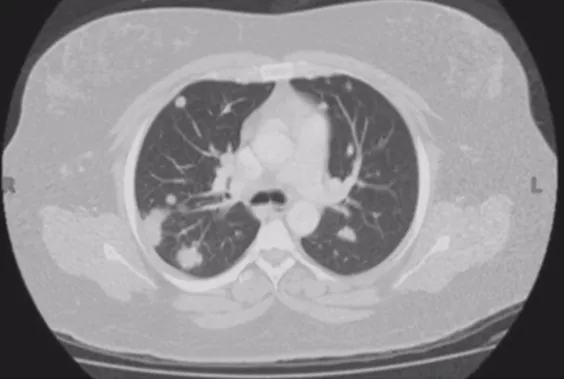

肺曲霉菌病

肺曲霉菌病可以表现为单发或多发的结节或肿块,边缘模糊,有的聚集成簇。感染早期可见胸膜下密度增高的结节影,病灶周围可出现晕征。发病10-15d后,肺实变区液化、坏死,可见空腔阴影或空气新月征。所以肺结节的鉴别诊断还要考虑是否存在曲霉菌感染。

晕征

晕征多见于良性病变,如肺曲霉菌病、卡波西肉瘤、肉芽肿病、血管炎(韦格纳)和转移性肉瘤。如果结节周围出现出血,可能出现晕征。但肺腺癌因附壁式生长也可以出现晕征。所以鉴别起来并不是很容易,要从多个指标观察。